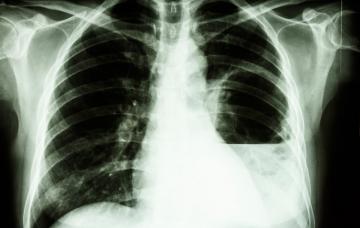

Diagnóstico de la melioidosis

El diagnóstico de melioidosis se basa en pruebas como análisis de sangre, radiografía de tórax, ecografia, TAC, e incluso cultivo de ciertas secreciones.